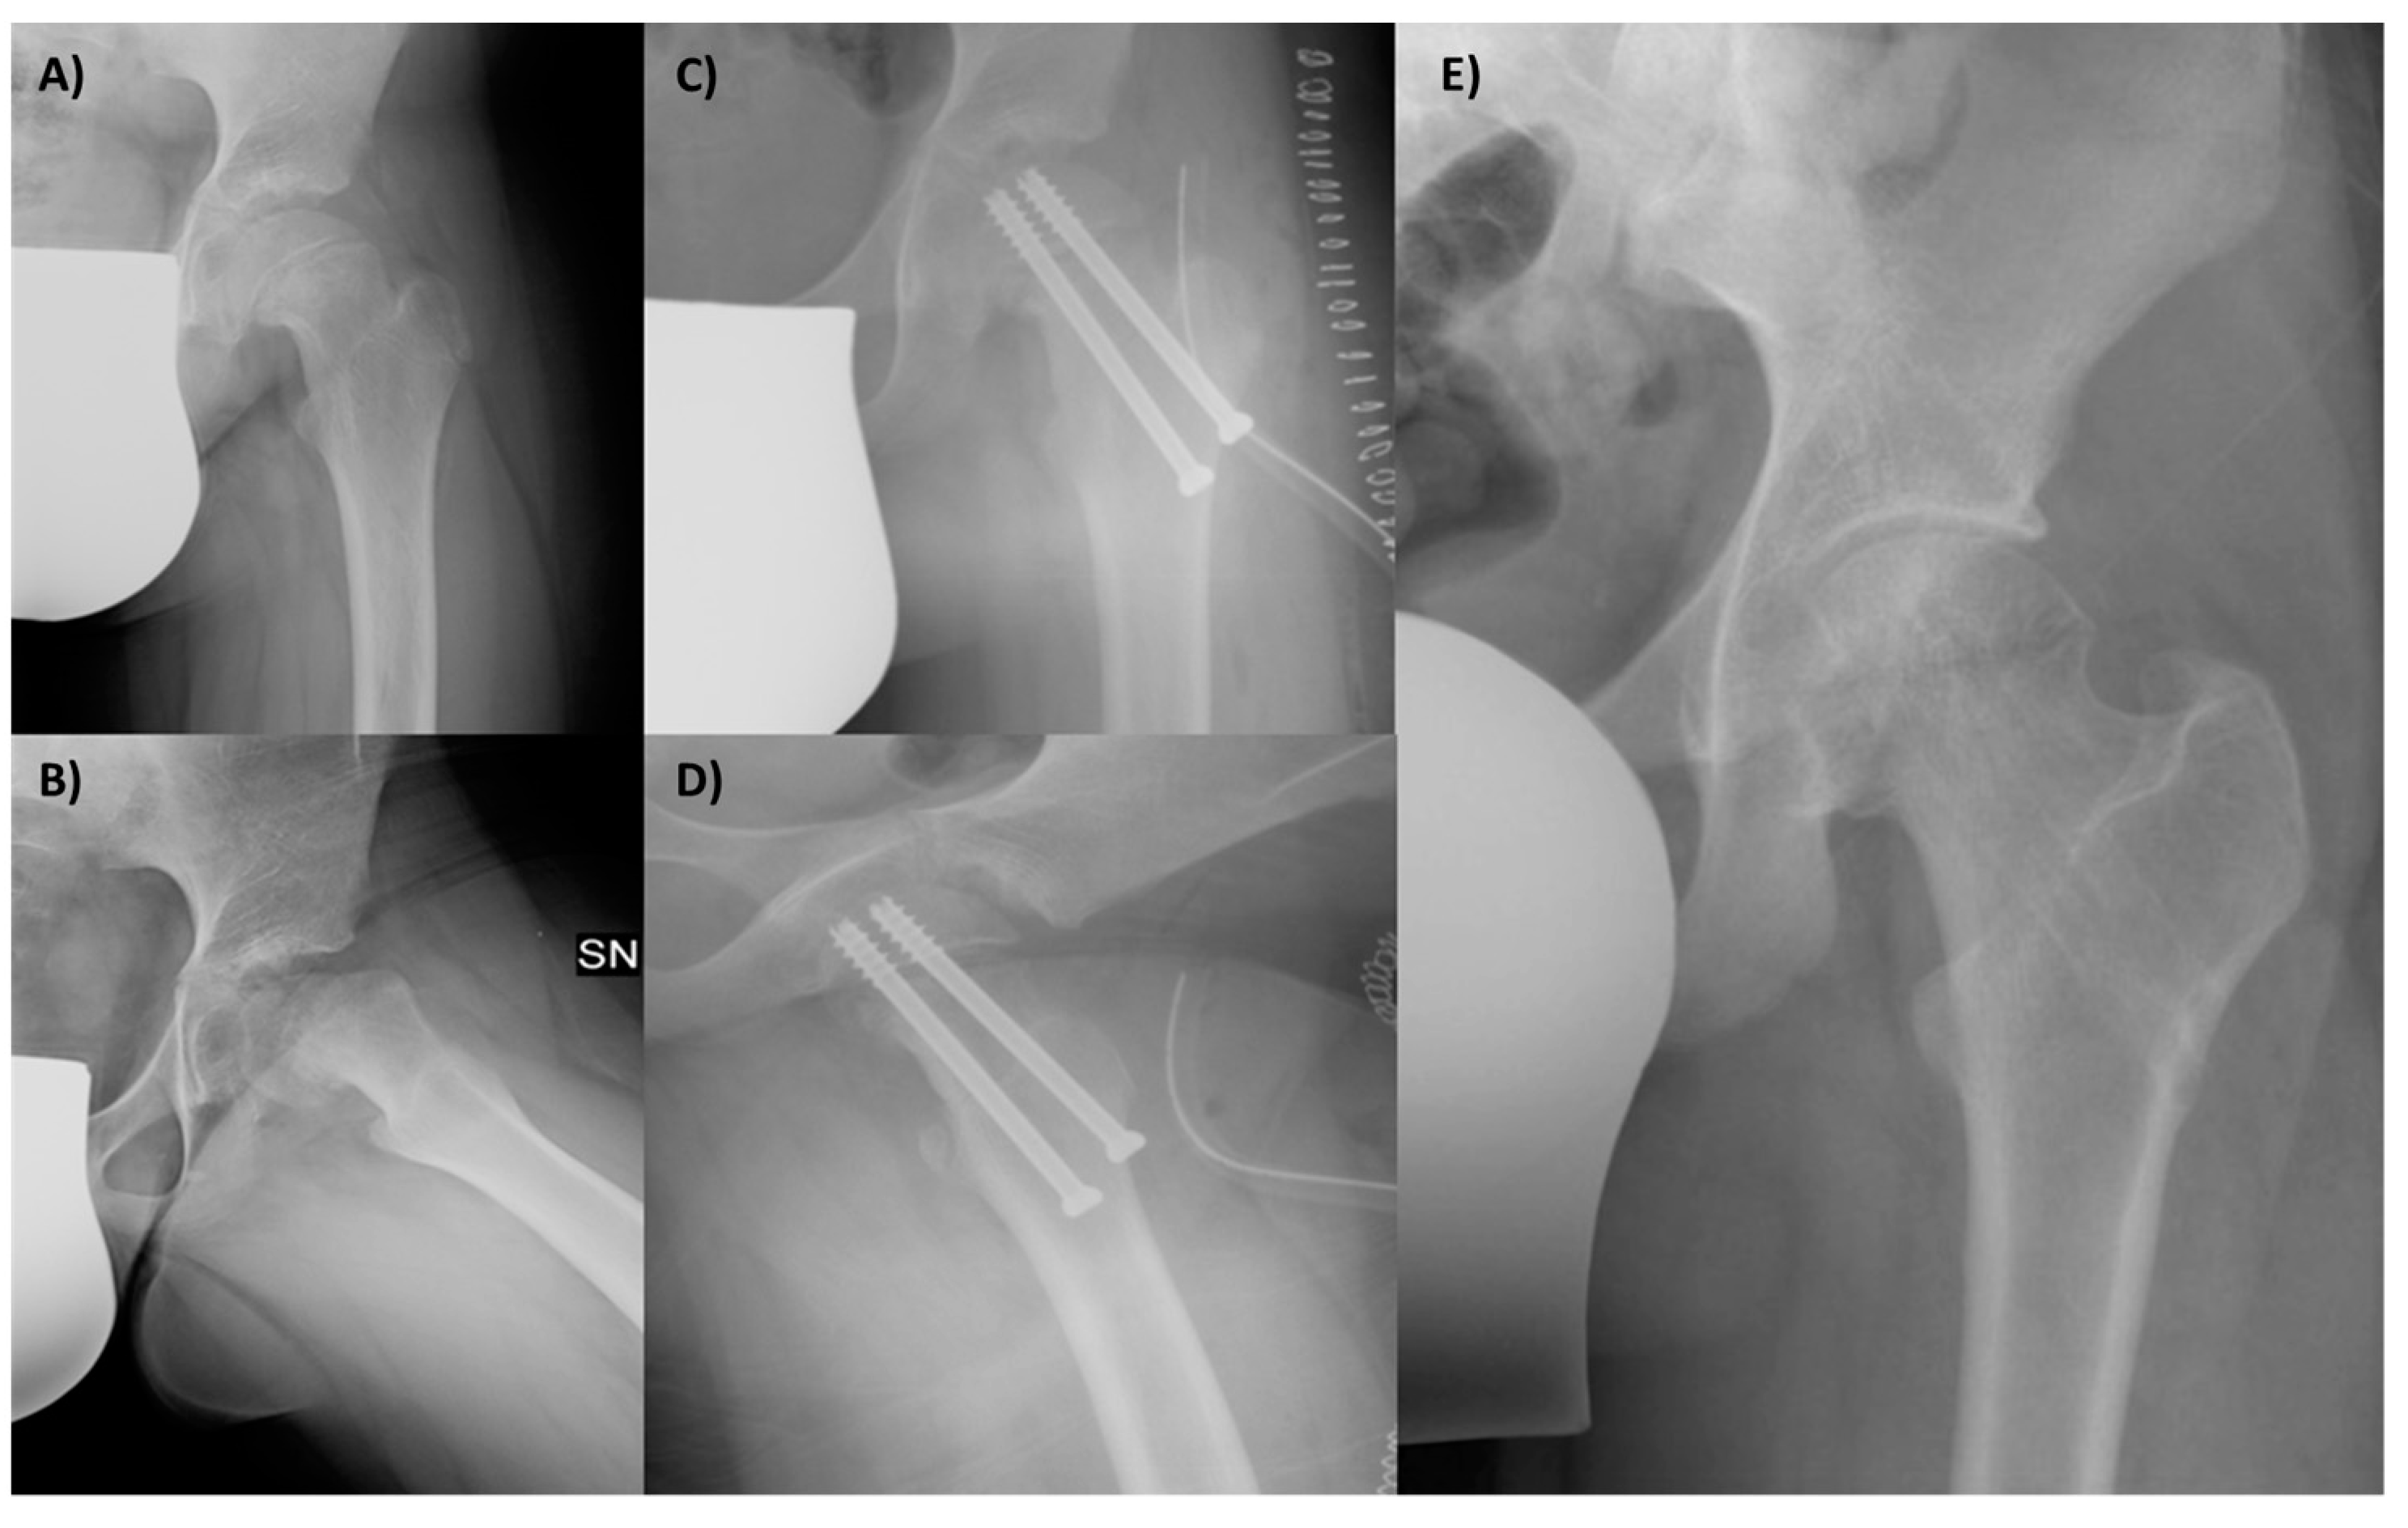

No major intraoperative complications occurred; there were three cases of postoperative transient deficits in the lateral femoral cutaneous nerve, resulting in thigh hypoesthesia. Fortunately, the hypoesthesia recovered within a year after the initial surgery. In one patient, 6 months after surgery, AVN of the femoral head occurred (1/24; 4.2% rate). This patient was treated 8 months before the index surgery for subacute SCFE reduction and percutaneous pinning. The patient was treated with the removal of the cannulated screws and no weight-bearing and crutches; in addition, physical therapy was performed. After 12 years, the patient developed secondary osteoarthritis and was treated with total hip arthroplasty (Figure 6).

Figure 6.

(A) Patient 10 months after VASSCO, after the removal of the cannulated screws. (B) After 12 years, secondary osteoarthritis developed, with severe limitations, which required total hip arthroplasty.